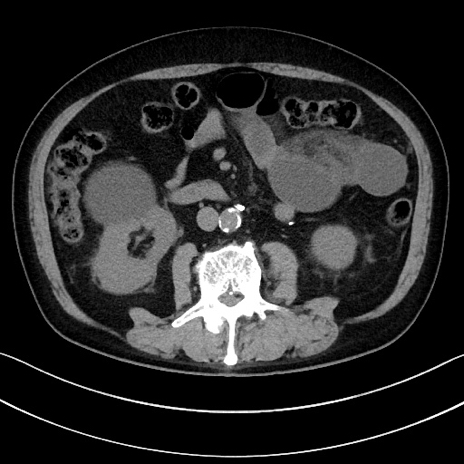

症例15(横断像)

【症例】70歳代男性

【主訴】腹痛

【現病歴】今朝から腹痛あり。全体的に痛い。特に左上の方。排ガスが今日はない。冷や汗が出る。

【既往歴】直腸癌術後

【身体所見】左側腹部〜上腹部に圧痛あり。腹膜刺激症状明らかなではない。軽度反跳痛。左下腹部に術後瘢痕あり。

【データ】WBC 7700、CRP 0.02